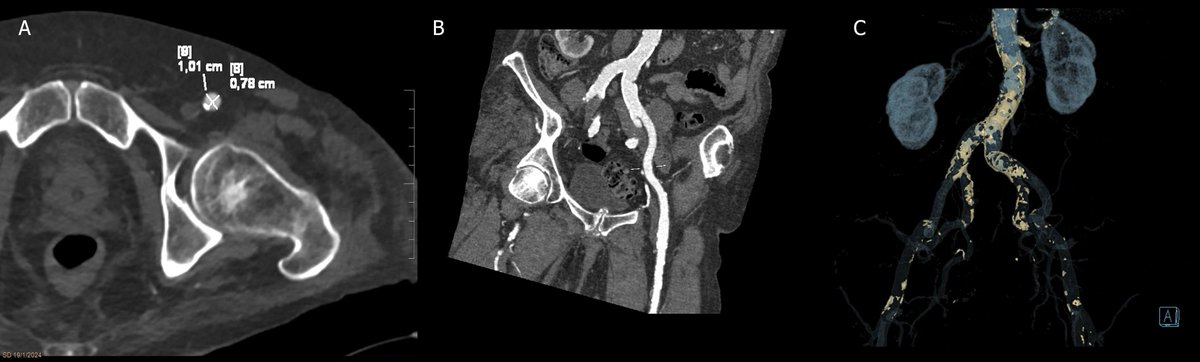

Y Radiología en imágenes presenta tres interesantes revisiones sobre las fístulas arteriales intraabdominales, el tumor desmoide y causas de fallo del implante coclear